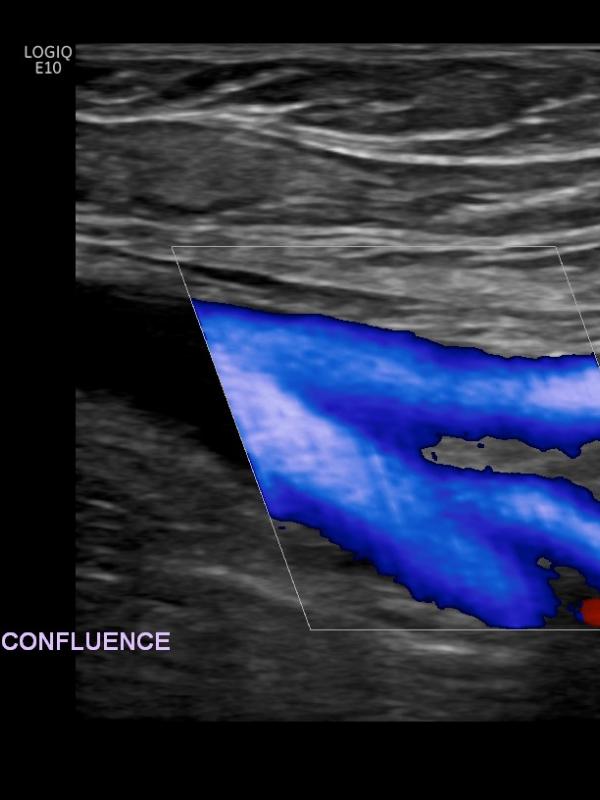

Venous ultrasound

Ultrasound imaging of the venous system is used to evaluate the vessel and returning blood flow from upper or lower extremities. Referring providers order venous ultrasounds for a number of reasons. The most common reasons are: leg pain or swelling, varicose veins, or evaluation for a suspected blood clot.

Venous ultrasound FAQ

• What is the preparation for a venous ultrasound examination? There is no required preparation for a venous ultrasound.

• What is a vein mapping ultrasound? A detailed evaluation of the entire venous system in your lower extremities. The sonographer will first evaluate for a blood clot, then will map out the superficial venous system and evaluate for valve incompetency